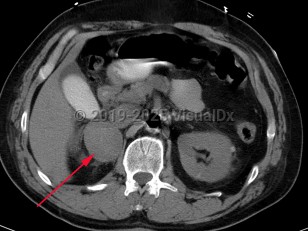

Pheochromocytoma

The majority of PCCs are intra-adrenal and solitary. Approximately 10% of all catecholamine-secreting tumors will be malignant. PCC may occur at any age but has the highest prevalence in individuals aged 20-50 years.